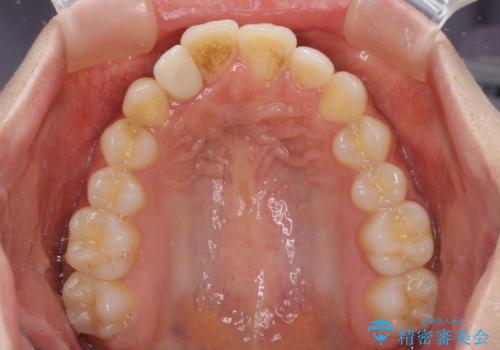

- 上下前歯のデコボコを気にして来院された患者様です。

前歯のセラミックが装着されている歯は、歯根が短くなっており、他院では抜けてしまうので矯正はできないと言われていたようです。

患者様と相談し、抜けてしまった場合にはインプラントあるいはブリッジによる補綴治療が必要となることを確認し、極力歯根に負担のかからないような仕上がりで治療を進めて行くこととしました。

デコボコを解消には、IPR(歯と歯の間を削る)をメインに歯列排列を設計し、インビザラインにて矯正治療を行うこととしました。

レントゲン写真上では、矯正治療前後で歯根長さに大きな違いはなく、抜歯を回避することができました。

上顎内側に転位している前から2番目の歯は移動が難しく、無理矢理歯根全体を動かそうと設計すると、歯肉退縮・歯髄壊死・歯根吸収といった危険性が増すため、無難なゴールにて治療を終えることとなりました。